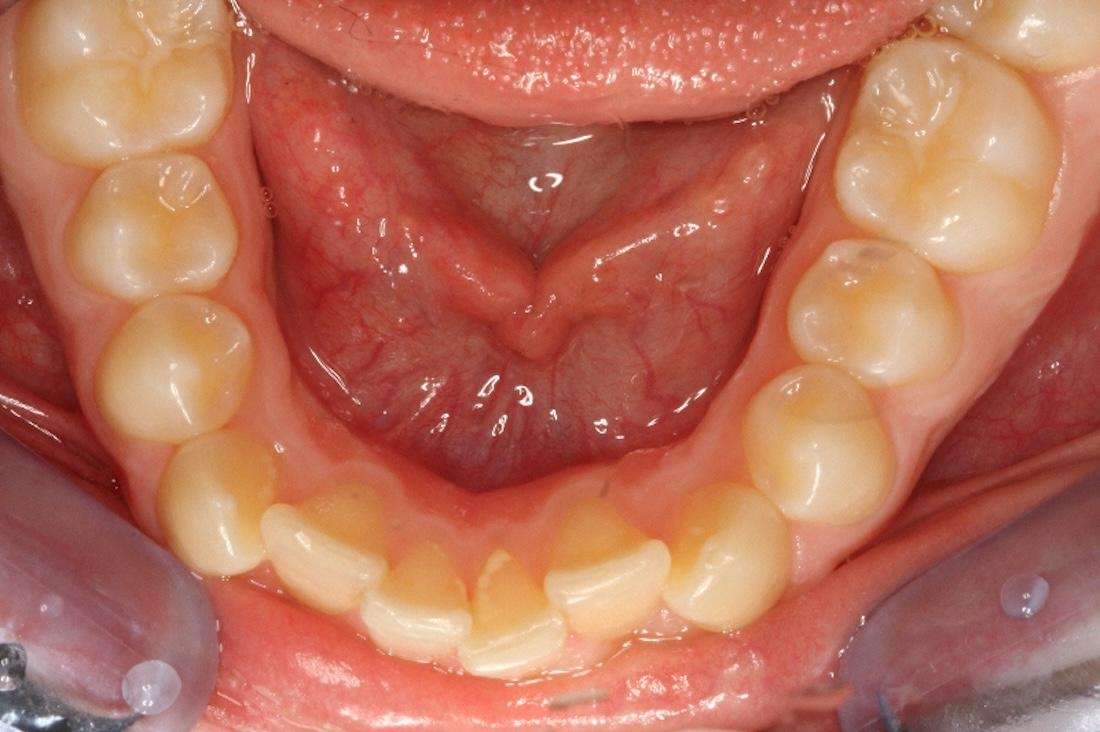

Before

After